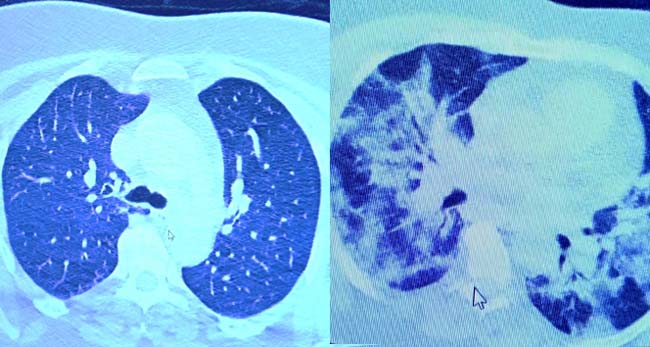

VM Medical Park Samsun Hastanesi’nde görev yapan Göğüs Hastalıkları Kliniği’nden Prof. Dr. Şevket Özkaya da bir hafta ilaç kullanmayan bir pozitif hastanın akciğer tomografisini inceledi. Hasta pozitif haldeyken ilk akciğer tomografisine bakıldı. Tomografide akciğerlerdeki tutulmanın az olduğu gözlemlendi. Akabinde aynı hastanın verilen ilaçları kullanmamış ve 1 hafta boyunca tedaviye uymamış haldeki akciğer tomografisine bakıldı. Sonuç ise ilaç kullanımının önemini ortaya çıkardı. Hastanın akciğer tomografisinde yaygın buzlu camların ve hava yollarının hava yerine ciddi şekilde sıvı ile dolduğu gözlemlendi.

Akciğer tomografisinde oluşan değişim ile ilgili bilgi veren Prof. Dr. Şevket Özkaya, "Ekranda 55 yaşında bir kadın hastamızın filmini görüyorsunuz. Bu kadın hastamız acil servisimize ateş şikâyetiyle geldi ve korona virüsünden şüphe ettik. Testini yaptığımızda ise testin sonucu pozitif geldi. Tomografi çektiğimiz zaman akciğerlerinde henüz ciddi bir tutulum görünmezken hastamız 55 yaşında olduğu için her an ilerleyebilir korkusuyla Sağlık Bakanlığımızın önerdiği ilaçları ve reçeteyi hastanemizden kendisine verdik. Hasta kendini evde karantinaya aldı fakat sonradan öğrendik ki tereddüt ettiği için ilaçlarını kullanmayarak kendini evde tedavisiz bırakmış. Yaklaşık bir hafta sonra aynı hasta acil servisimize bu sefer solunum yetmezliği şikâyetiyle geldi. Solunum yetmezliği gelişince hastanın akciğer tomografisinde ‘buzlu cam’ dediğimiz ve daha ileri konsolide alanların oluştuğunu gördük. Yaygın akciğer harabiyeti dediğimiz bir tablo oluşmuştu. Bu durumda hastada solunum yetmezliği olduğu için yoğun bakıma almak zorunda kaldık" dedi.